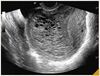

23a, 2ª consulta PN, assintomatica 1. Interpretar exames e orientacoes 2. Qual sindrome exclusiva desta gestacao e complicacao mais temida?

Apresentar-se (nome e funcao) 1. Calcular IG pela DUM Calcular IG pela USG de 1º Trim Determinar se as IGs sao compativeis Identificar Rh (-) e CI (-) Orientar Ig-Anti-D em 28s Suscetivel a Toxo Medidas de prevencao a toxo Imune a Hep-B e nao vacinar Sinal do T no USG e identificar gestacao gemelar monocorionica 2. Sind Transfusao Feto-Fetal